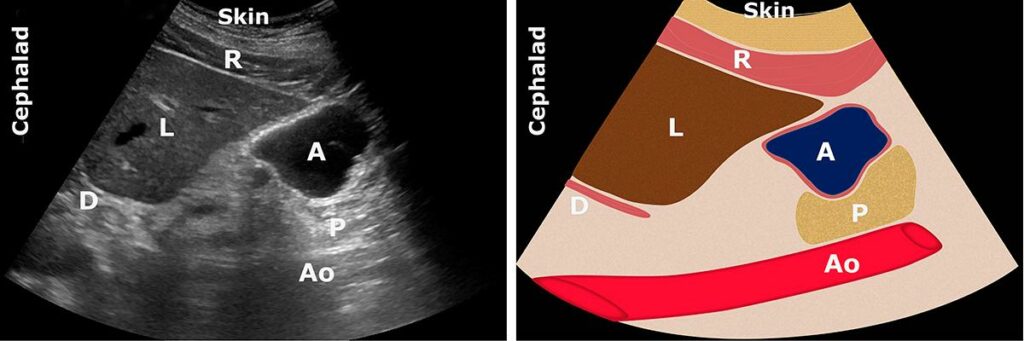

BERRAK SIVI

A: Antrum; Ao: Aort; C: Kolon; L: Karaciğer; P: Pankreas;

https://www.gastricultrasound.org

Antrum yuvarlak, distandü ve ince duvarlıdır. İçerik anekoik veya hipoekoik görünür. Antrum boyutu mide hacmi ile orantılıdır. Antrum, sırtüstü pozisyona kıyasla RLD’de daha büyük görünecektir. Hacim değerlendirmesi, düşük (normal) miktarda temel mide salgısını daha yüksek (açlık olmayan) bir hacimden ayırt edebilir.